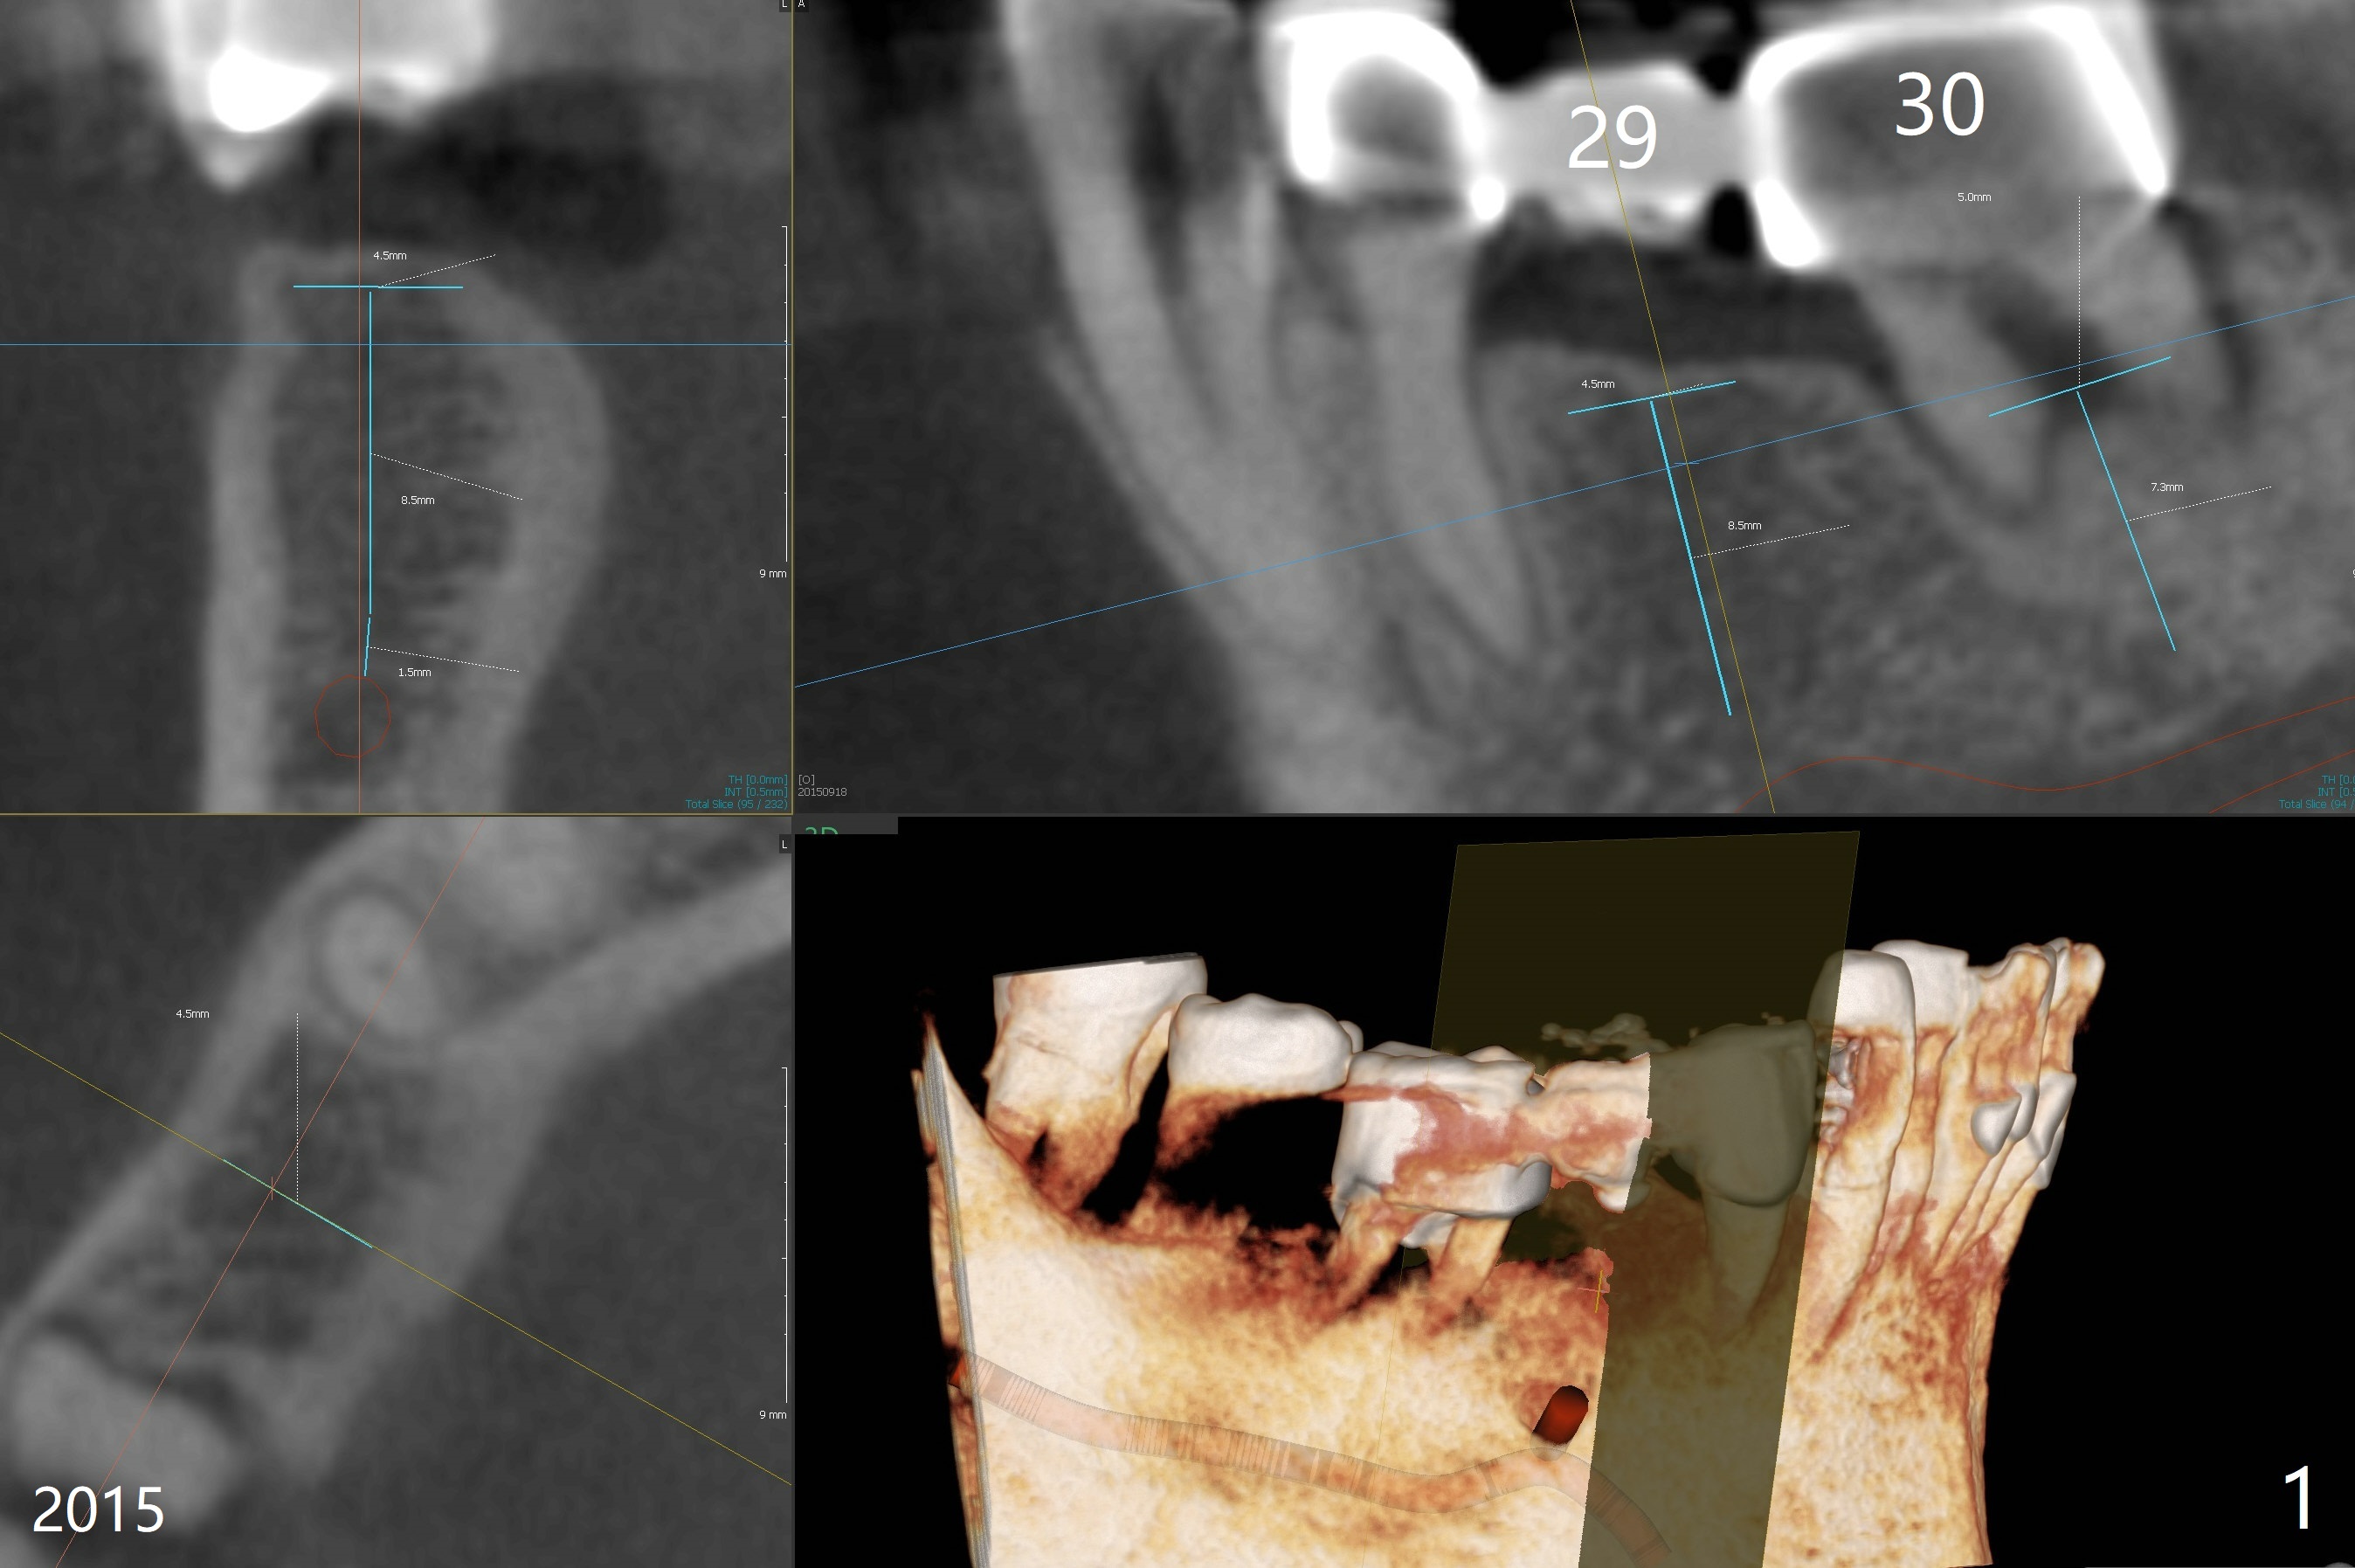

A 55-year-old man had #30 extracted and #29 pontic removed ~ 3 months ago (Fig.1,2). Short implants are to be placed (4.5x8.5 and 5x7.3 mm) with guide. Pay attention to the submandibular fossa (Fig.2 *) as related to the site of #30. New CT (Fig.3,4 (2018)) shows that implants will be 4x7.3 and 5x7.3 mm.